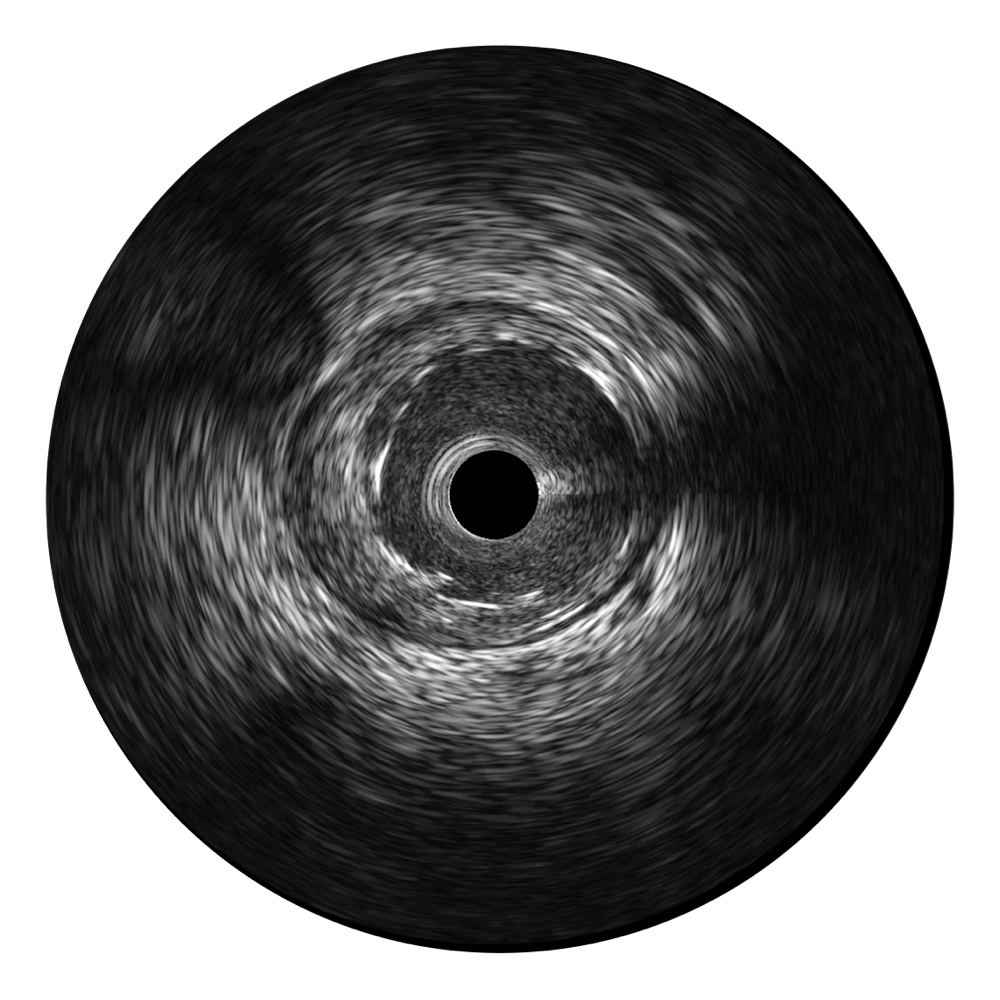

云顶集团官网超宽频成像技术覆盖20-80MHz1或20-90MHz2频率范围, 提供优异的分辨力同时也保证充足的穿透深度

对比传统IVUS导管成像,云顶集团官网宽频IVUS图像的近场支架梁显影更细腻,远场中膜外血管仍清晰可辨,兼顾远中近,兼顾分辨力与穿透深度